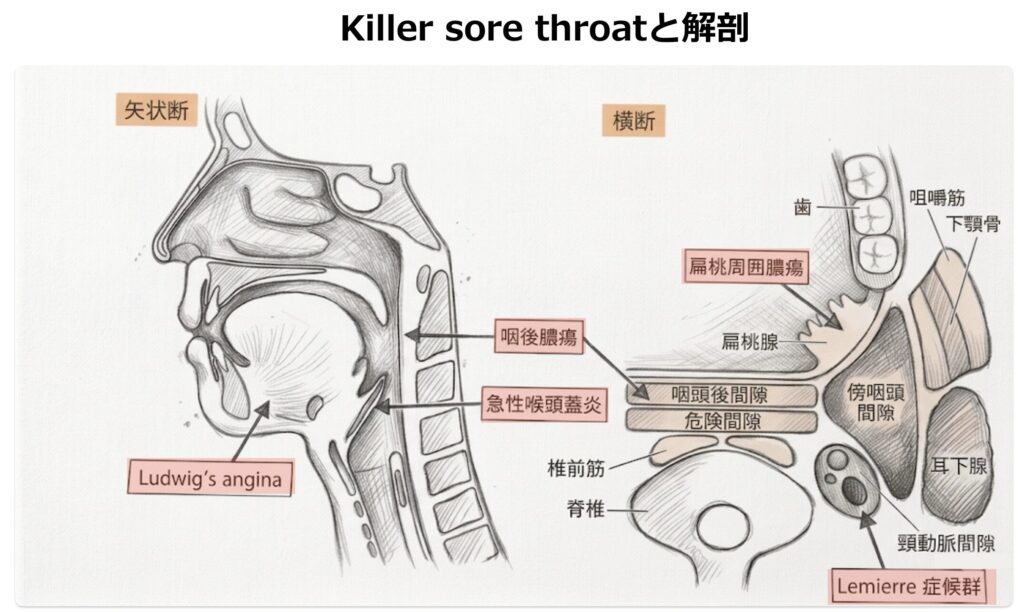

- 今回は以下のkiller sore throatをきたす疾患たちを深ぼっていきます。

- 急性喉頭蓋炎

- 扁桃周囲膿瘍

- 咽後膿瘍

- Ludwig angina

- Lemierre症候群

急性喉頭蓋炎 (epiglottitis)

扁桃周囲膿瘍(Peritonsillar Abscess)

咽後膿瘍 (Retropharyngeal Abscess)

Ludwig’s angina(口腔底蜂窩織炎)

Lemierre症候群